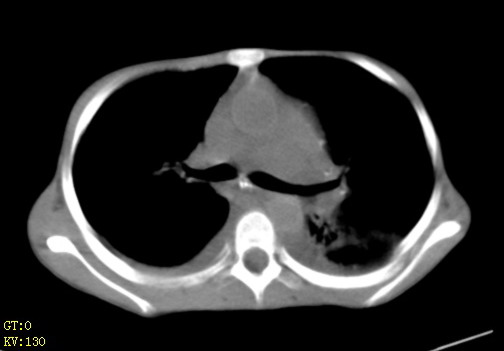

女,12岁,气促、咳嗽2天,3个月前查胸片示:两肺感染,急诊入院查ct,血常规等未检查。

两肺炎症,少量胸水;建议抗炎治疗后复查。

两肺感染,双侧少量胸腔积液;肺淤血及心脏改变,考虑心功能不全改变。学习了,望能反馈随访结果。

1)考虑两肺感染性病变;建议抗炎治疗后复查。2)双侧少量胸腔积液。